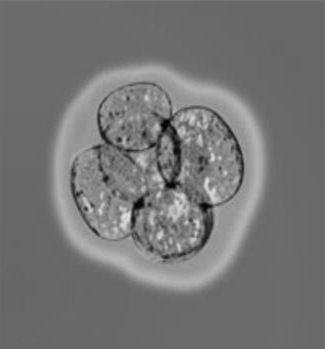

传统的小鼠胚胎干细胞是在小鼠胚泡(blastocyst)阶段取得的,胚泡阶段是小鼠受孕后的3~4天之间;而新型干细胞则是从胚胎中的一个叫做外胚层(epiblast)的结构中获得的,此时胚胎发育了一周,已能够把胚胎移入子宫。